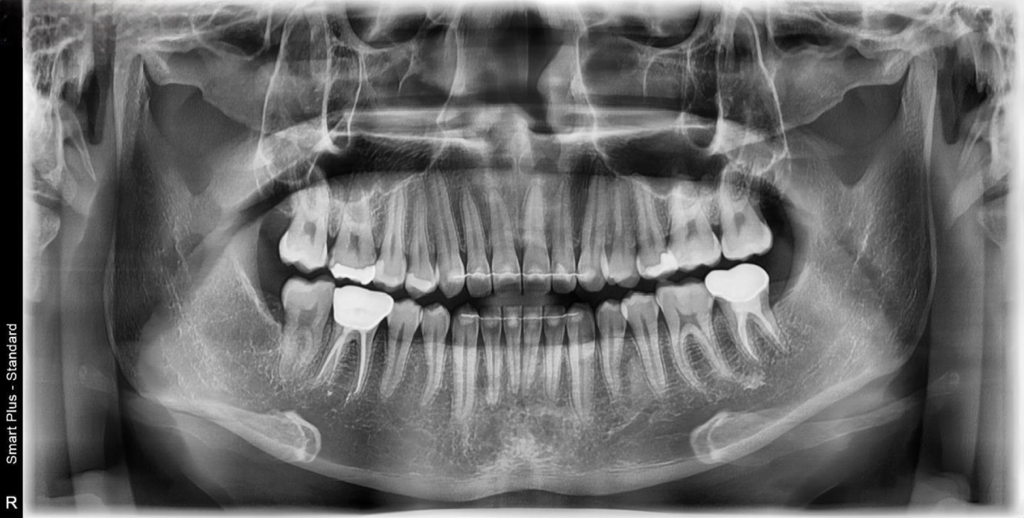

안녕하세요 치아에 관해 큰 돈이 깨진 기억이 있어 꾸준히 3개월마다 간단한 검진을 진행해 왔습니다. 이번에도 마찬가지로 3개월 가량이 되어 스케일링 및 검진을 위해 최근 개원한 치과에 초진을 보러 갔고 엑스레이 사진 상 왼쪽 위 앞쪽 뒷쪽 어금니에 인레이 치료 두 개 오른쪽 아래에 치아 마모된 부분은 레진 치료 진행해야 한다고 하시더군요 치아 번호로 말씀드리면 24번 27번 인레이 치료(필수) + 25,26번 레진(인레이 치료 도중 충치 발견시 레진 치료 가능성 높음) + 45번 치아 마모된 부분 레진 치료

이렇게 진단을 받았습니다. 제가 따로 보험도 없고 현재 복무중인 입장이라 한 달 월급보다 더 큰 비용이 치과로 나가야 한다는게 너무 두렵네요 ㅠㅜㅜ 3개월 마다 검진 및 스케일링도 꾸준히 관리 했는데도 충치가 발견되어서 속상합니다. 충치 치료에 관한 조언과 이 치아를 관리로 최대한 살려볼 수 는 없을지 아하 전문가님들의 조언을 구하고자 글 작성합니다. 참고로 위 치아들에서 통증은 전혀 느껴지지 않았고 45번 치아에 치과 바람 기계? 쏠 때만 시림을 느꼈습니다.

엑스레이 상으로 충치가 엄청 깊어 보이거나 하지는 않습니다. 물론 충치치료의 판단은 엑스레이도 중요하지만 육안으로 직접보고판단을 해야됩니다. #45번의경우에는 바람에만 시리면 치경부 마모증일 가능성이 있습니다. 인레이의 경우에는 엑스레이만 보고는 판단하기는 어려울것같습니다.